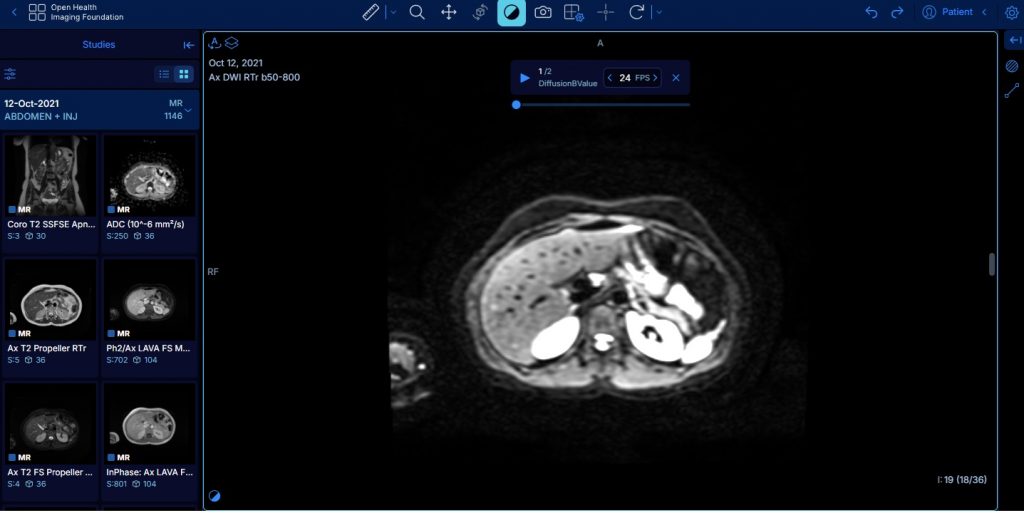

↪ Dans l'attente : expérimentation au sein de K-Process d'un espace de mise en partage temporaire des examens DICOM.

Les besoins des équipes RCP et l’absence de solution immédiate suite à l’arrêt programmé du module Krypton nous conduisent à la mise en œuvre prochaine d’un espace de partage temporaire d’examens DICOM autour de la RCP.

• proposer une visionneuse basique directement accessible depuis le navigateur web.